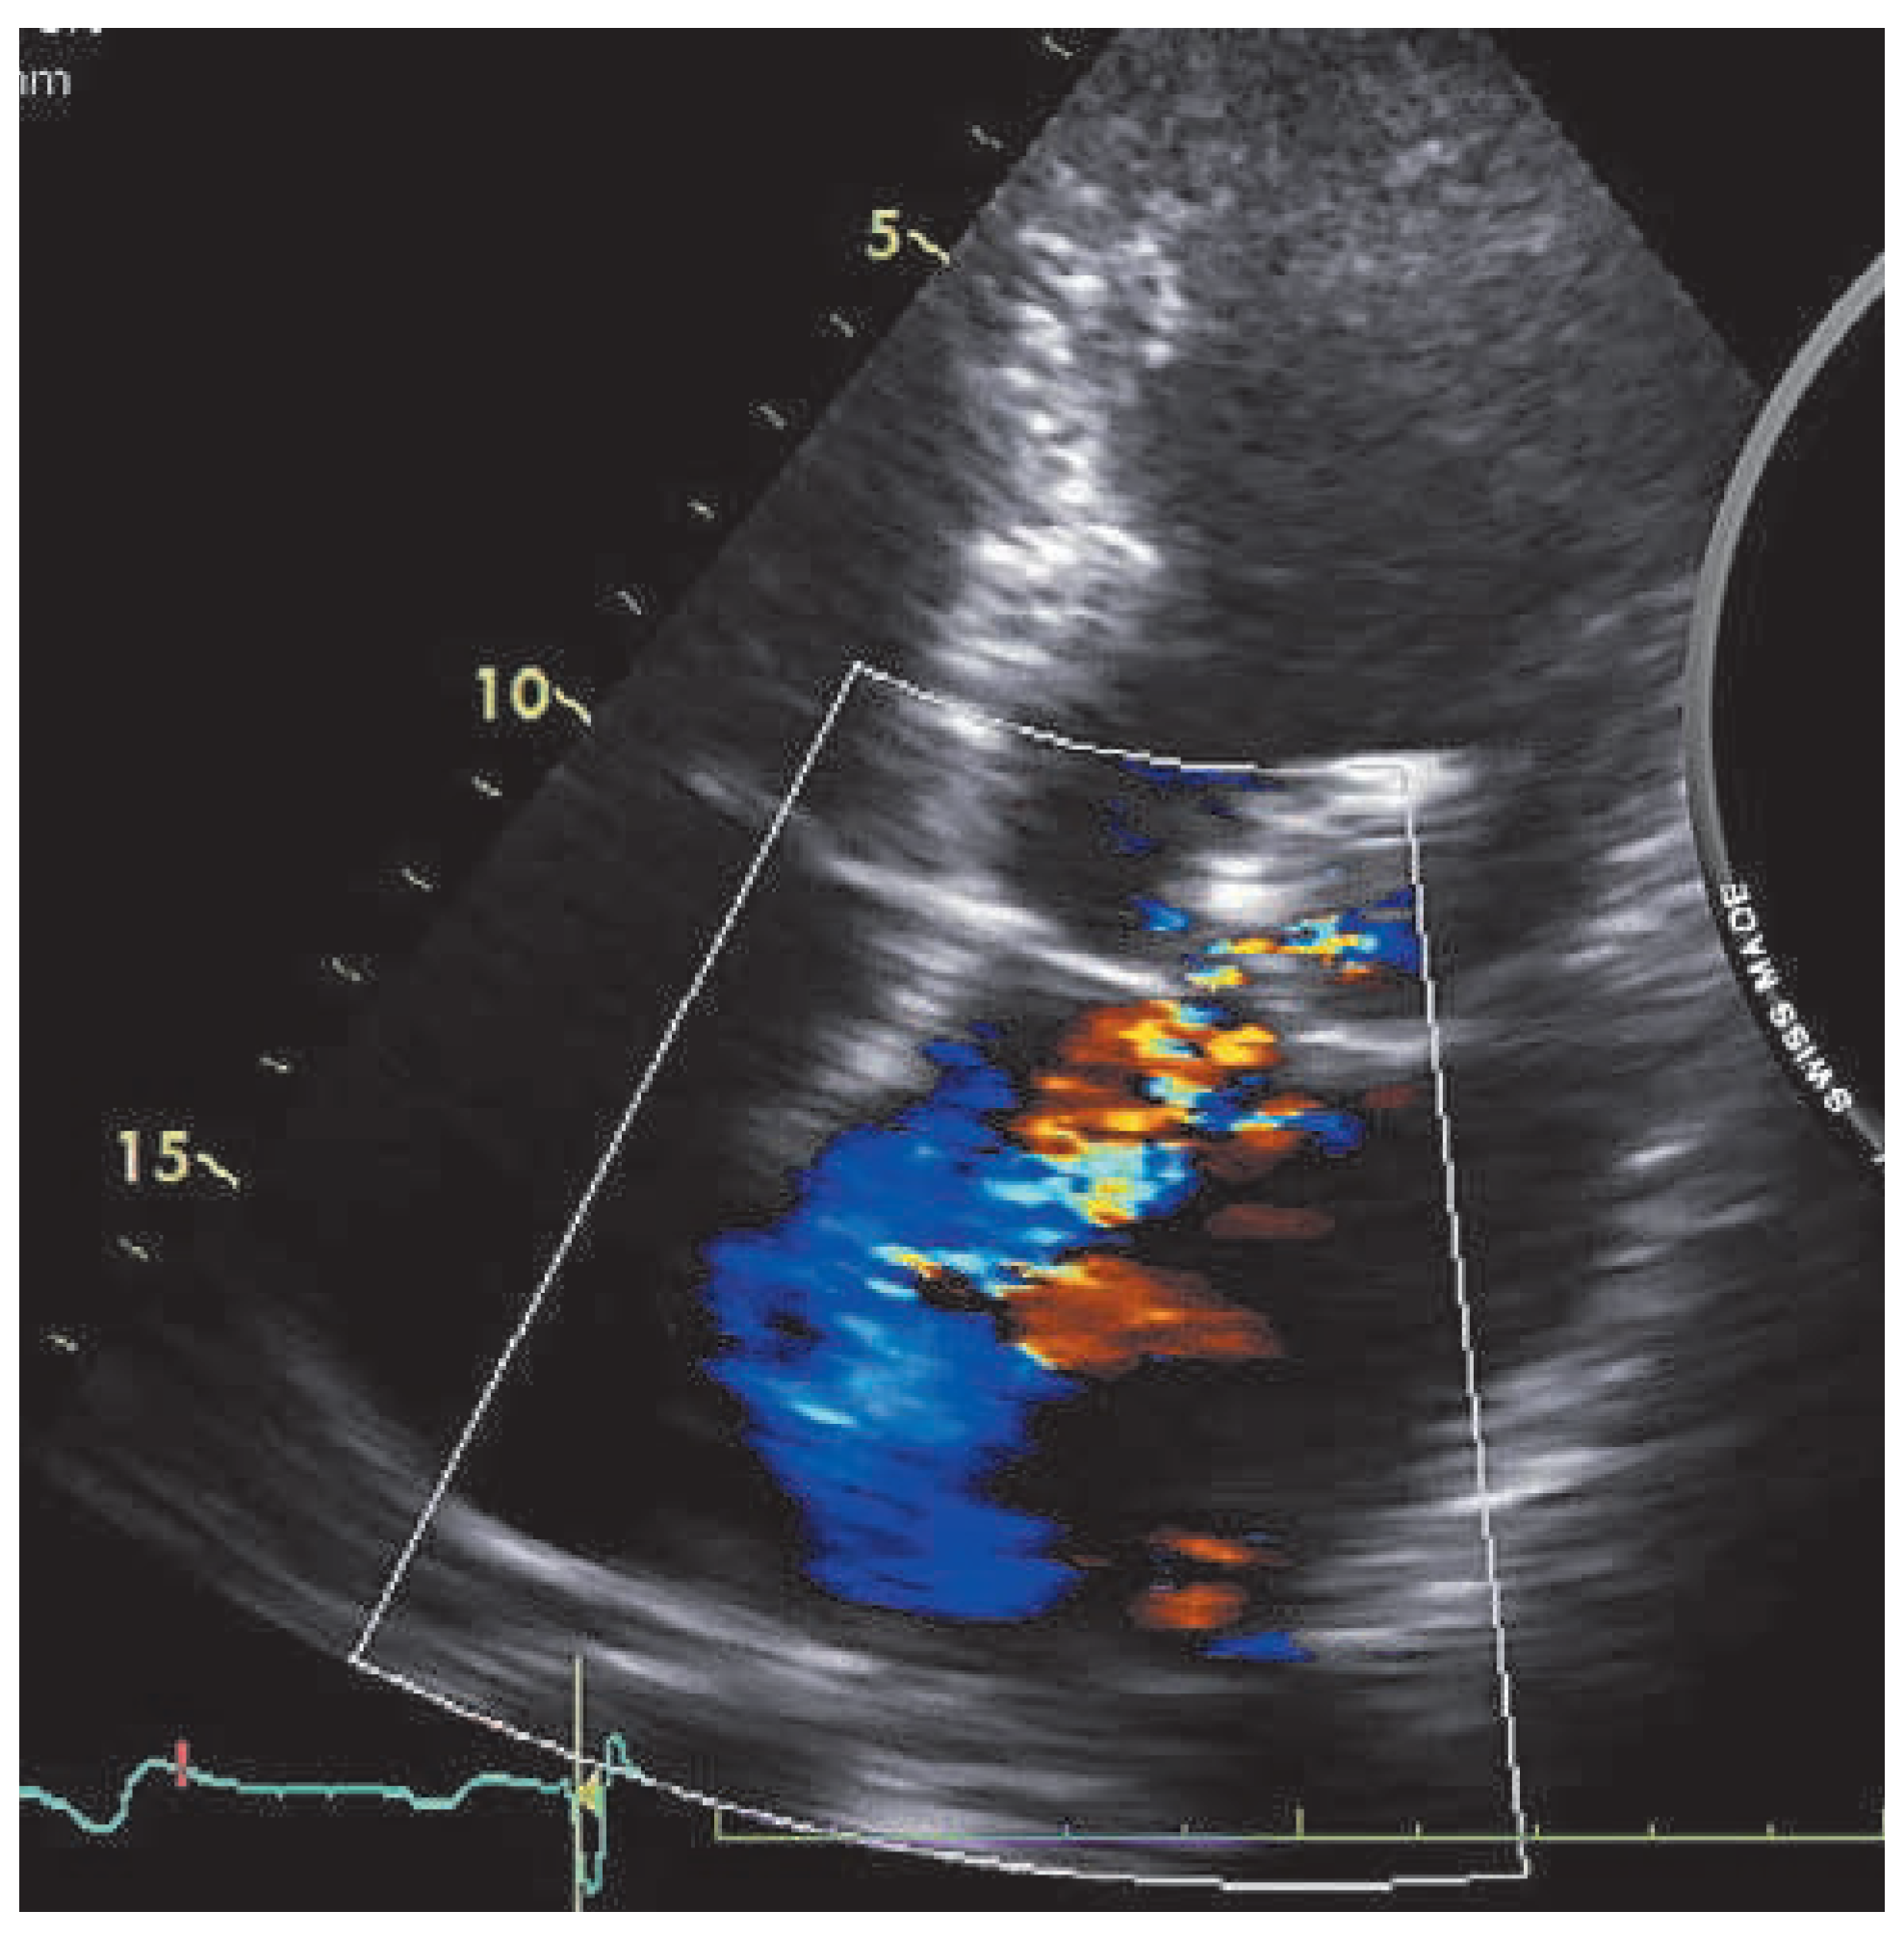

A 59-year-old man was referred to our institution for dyspnea. He had a history of mitral valve regurgitation with posterior leaflet valve prolapse. In 2006 he underwent mitral repair without annuloplasty ring implantation. In April 2012 dyspnea, NYHA II–III, recurred. Echocardiography showed grade III to IV mitral regurgitation. He was referred to another hospital, where percutaneous treatment with MitraClip™ implantation was proposed to the patient. Two MitraClips™ were implanted. Shortly after the intervention the patient complained about shortness of breath. He was seen at our hospital. Transthoracic echocardiography (Figure 1) and cardiac computed tomography (Figure 2) confirmed the clinical impression of both mitral stenosis and regurgitation with significant gradient and a valve surface of 1.7 cm2. M-mode echocardiography showed typical patterns of mitral stenosis (Figure 3). Mitral valve repair with annuloplasty could be performed with neocordals, reinforcement of the posterior leaflet and ring implantation (Figure 4 and Figure 5). Six months later, the mitral valve is fully functional and the patient is asymptomatic. This case is remarkable for a few points: firstly, mitral annuloplasty with ring implantation should be performed instead of simple repair. Secondly, equivalence of surgery with MitraClip™ implantation has been proven in some trials. However patients included in these studies were older and sicker than our patient. There are more arguments to suggest that MitraClip™ should be reserved for nonoperable patients or to patients refusing surgery. In our patient, revision surgery was probably a better option than a percutaneous approach. Valve dysfunction requiring a second intervention is almost 10 times more frequent after MitraClip™ implantation than after conventional surgery. Thirdly, even though trials about MitraClip™ are still ongoing, indications should not be lifted to younger patients, until we have clear evidence regarding the comparison of the 2 techniques. Finally, mitral valve repair with annuloplasty and ring implantation is possible after MitraClip™ implantation.

Figure 1. 2D echocardiography showing mitral regurgitation.